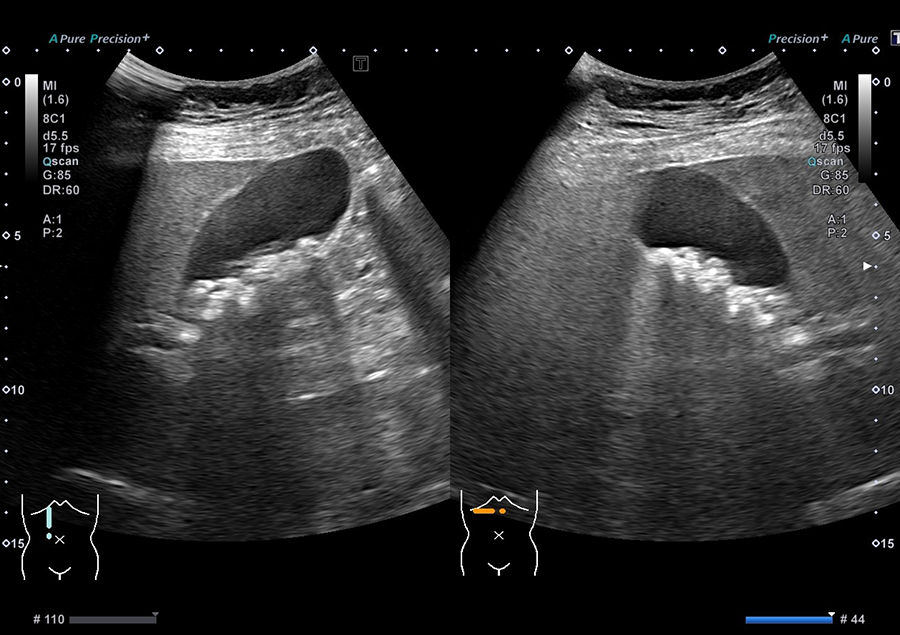

02.最新の超音波診断装置を導入

当院では、キヤノンメディカルシステムズ株式会社の超音波診断装置「Aplio a Verifia」を導入しています。

- ノイズを低減し、クリアな画質で病変を検出

- 従来の腹部エコーに比べ、広範囲を一度に撮影可能で、病変の位置がより分かりやすく確認できます

- 送信・受信技術(Advanced Sync Pulser と Advanced Beam Receiver とMulti-Harmonic Compounding)により、高精細な画像を提供

- 低流速血流の観察に適したSMI で、病変を詳細に観察

高精細な画像と優れた解析技術により、正確に観察することが可能です。